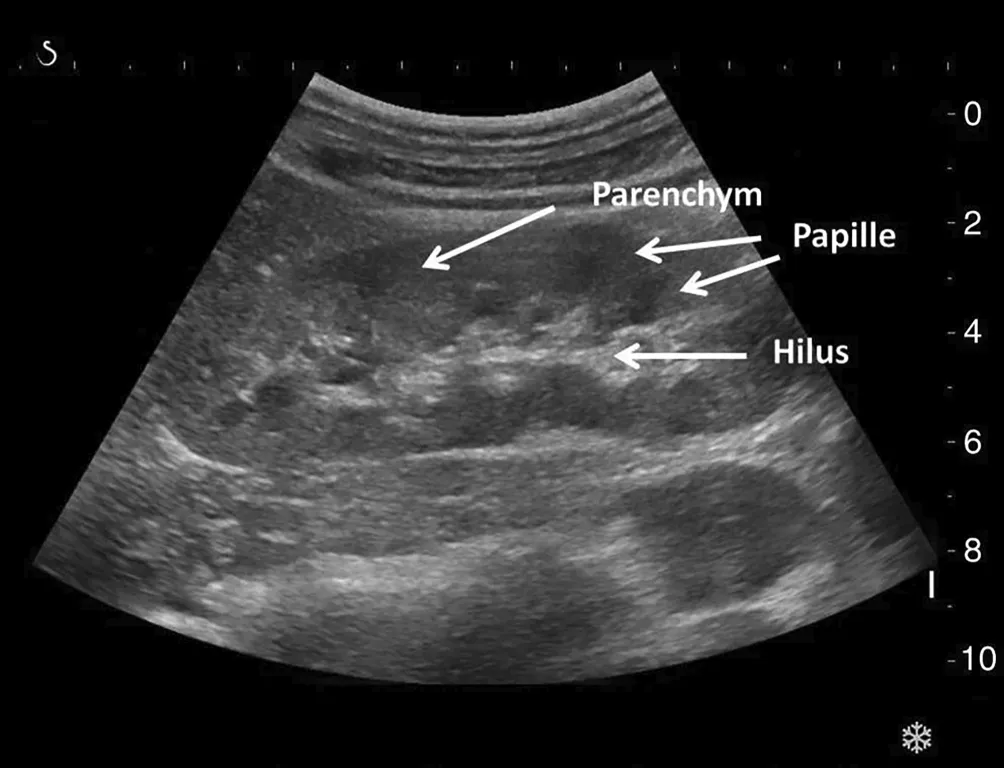

Ultraschall als Standard: Was die Sonographie Ihrer Nieren zeigt

Der Ultraschall (Sonographie) ist die Standardmethode zur Untersuchung der Nieren. Mit Schallwellen können Größe, Form und Beschaffenheit der Nieren dargestellt werden. Auffälligkeiten wie Zysten, Tumore oder ein Harnstau lassen sich so gut erkennen. Bei einer fortgeschrittenen chronischen Nierenschädigung zeigen sich die Nieren im Ultraschall oft typischerweise verkleinert, und die Nierenrinde, die funktionell wichtigste Schicht, ist verschmälert.